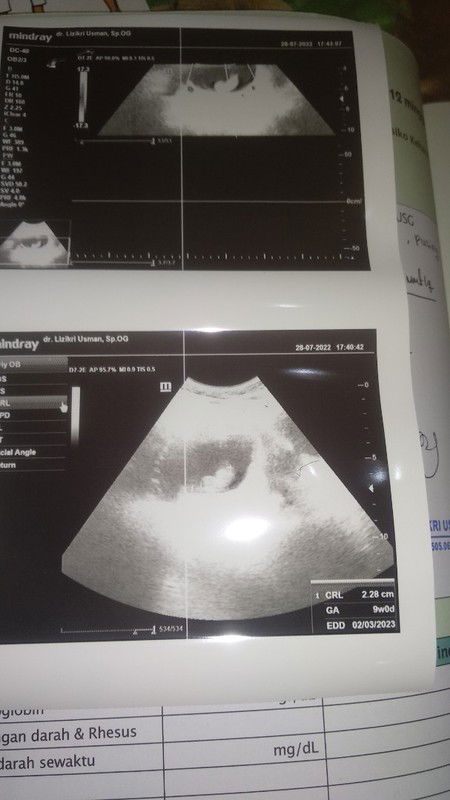

Hari ini saya habis USG yg kedua bun diusia kehamilan 10 week. Ini adalah kehamilan kedua saya setelah keguguran bulan Agustus 2022 lalu. Sepanjang jalan menuju RS deg2an bgt bun karena msh takut dan khawatir dengan riwayat keguguran dulu. Saya juga sempet USG usia 6 week tp masih kantong saja, jd sedikit menambah kekhawatiran saya. Sepanjang jalan saya gak pernah berhenti sholawat bun. Saking deg2annya pas cek tensi darah saya diangka 110 (biasanya saya cek selalu dibawah 100). Saya juga pegangin terus tangan suami dan bilang ke dia, sy tegang banget. Dia sih menanggapi santai aja sambil main hp. Akhirnya tiba giliran saya untuk periksa. Sy ceritakan semua keluhan saya ke dokter. Dan... Masyaa Allah Alhamdulillah bun ... Bayinya udh ada dan djj nya juga sudah kedengaran. Ditunjukin sama dokter. Sy speechless bgt mau nangis rasanya denger djj anak saya yg pertama kali 🥺🥺🥺 dan alhamdulilah adeknya sudah bisa gerak usia sesuai HPHT 10 week. Dokter minta suami saya mengabadikan momen ini lewat video. Seneng bgt bun rasanya perjalanan pulang gak berhenti saya senyum. Rasanya jd semangat banget mau makan lebih sehat, yoga, dan minum vitamin. Nyampe rumah udh ashar. Saya dan suami sholat ashar. Eehhh sy kaget bgt denger suara sesenggrukan. Ternyata suami saya lagi nagissss 😭😭😭 Ya Allah ternyata hati dia lembut banget. Saya gak tega liat suami nangis terharu kaya gitu akhirnya kita nangis bareng sambil pelukan. Momen yg gak akan pernah sy lupakan. Suami sambil nangis bilang, dr tadi aku juga takut banget dan cemas. Tp aku pura2 kuat biar km gak tambah khawatir. Masya Allah tabarokallah... Sy makin jatuh cinta bgt sama suami saya bun.. ternyata hati dia lembut bgt dan sayang bgt sama aku dan calon anaknya. 🥺🥺 Mohon doanya ya bun semoga kehamilanku kali ini sehat2 dan lancar sampai persalinan. Aku doakan juga semoga bunda2 yg sedang mengandung juga diberikan kesehatan dan kelancaran 🤗 Makasih ya udh mau denger curhatan aku ya bun 🤗🤗 #firstmom #firstbaby